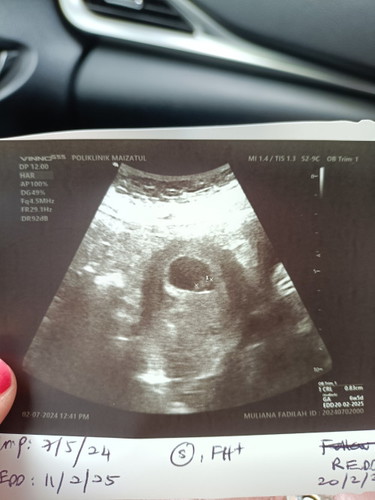

Dah ada bunyi jantung

Selepas bleeding masa minggu ke 5, tadi scan dah nampak janin dan dengar bunyi jantung.. alhamdulillah..